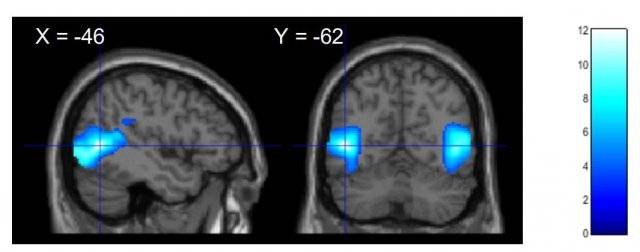

감동은 자기를 비판하고 부정적인 감정에 몰두하도록 만드는 뇌의 영역에도 영향을 미친다. 지난해 미국심리학회지에 실린 ‘경외감의 신경 표현: 일반적이고 뚜렷한 신경 메커니즘의 구별’ 연구에서는 fMRI(기능적 자기공명영상) 촬영을 통해 감동적인 영상을 볼 때 뇌에서 일어나는 활동을 분석했다.

영상의 내용은 아름다운 자연, 종교적 경험, 존경할 만한 리더의 모습 등 다양한 차원의 감동적 상황을 포함했다. 뇌 활동 비교를 위해 즐거움과 공포를 유발하는 영상도 각각 보여줬다. 관찰 결과 감동적인 영상을 시청할 때 자신을 비하하고 비판적으로 느끼게 하는 뇌의 왼쪽 중간 측두회(middle temporal gyrus)의 활성화 수준이 다른 영상을 시청할 때보다 낮아졌다. 감동을 느낄 때 자기 자신을 좀 더 너그럽고, 긍정적으로 바라볼 수 있게 되는 것이다.